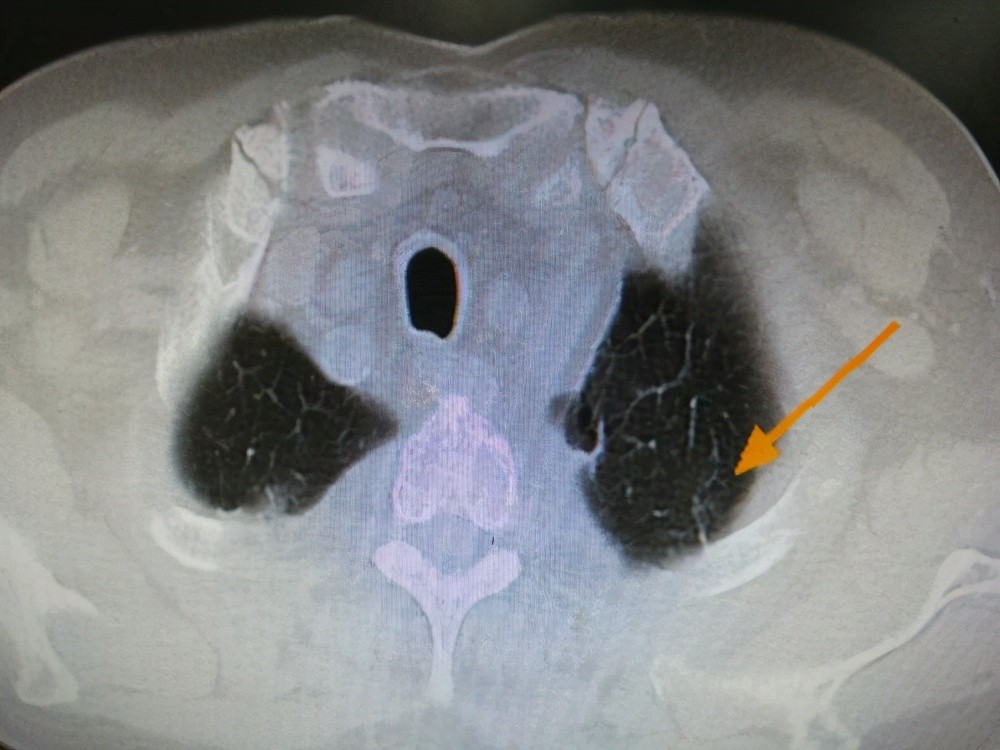

4.局限性肺气肿

局限性肺气肿是指CT所发现的局灶性肺气肿改变 , 面积不大 , 可伴有局部的肺大泡 。 当局部的某些气管狭窄 , 就只会引起局限性肺气肿 。 多见于长期吸烟者 , 另外支气管哮喘 , 慢性阻塞性肺病也有可能导致局限性肺气肿 。 大部分情况下 , 局限性肺气肿没有明显临床症状 , 也不需要特殊治疗 , 对肺功能影响较小 。 只需要注意平时肺部保养 , 减少有毒有害气体对肺部的损害 , 避免受凉、感冒并戒烟 。